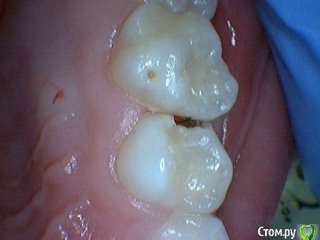

Давлетшин Опубликовано 29 декабря, 2017 Поделиться Опубликовано 29 декабря, 2017 (изменено) Друзья. Расскажите, не поменялось ли ваше отношение к пульпотеку и пр.Почему пломбы поверх пульпотеку такие ужасно жёлтые? Что сделать можно. Или что я делаю не так? "Друзья" так приятно перед новым годом. К пульпотеку не поменялось (устраивает вполне) , к пульподенту скептическое отношение, хоть и тоже работаю. Пломбы сразу желтые или через полгода - год- два? Очень тяжело что то советовать он лайн не видя как человек работает. В фото первая цифра пациент, вторая-третья номер зуба, четвертая порядок фото. Я после наложения пульпотека , стараюсь убрать излишки, или аккуратно на устья каналов накладываю, в пульповую камеру СИЦ, и сверху пломбу, Убрать излишки и со стенок, аккуратно в том числе и бором. В третьем клиническом случае, неудача. Зуб удалил сам же через 3 месяца. причину вижу в том что на рентгене не увидел (или так сделали снимок?) вертикальный тип рассасывания практически до бифуркации., может и потому что ребенок ОЧЕНЬ плохо сидел. За фото не пинайте сильно, не инстаграмм все таки,да и тяжело ребенка лечить и фотки делать. или наоборот пинайте может лучше начнем фоткать. P.s. Добавлю протокол как лечу с пульпотеком, хр.фибр.пульпит1. анестезия2. кофер ( если дает)3. раскрытие кариозной и пульповой камеры4. удаление коронковой пульпы маленьким эскаватором, я стараюсь "отрубать" пульпу5. остановка кровотечения сухим ватным шариком, 0,5-1-2 минуты6. пульпотек на устья7 СИЦ в пульповую камеру8 со стенок остатки пульпотека соскребаю бором фиссурным , цилиндрическим, там же фальц9. Пломба. может что то и зыбыл ну и оценка только позитивная перед НГ Изменено 29 декабря, 2017 пользователем Давлетшин 2 Ссылка на комментарий